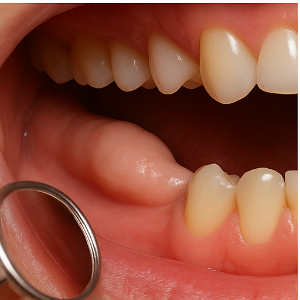

치과에서는 대부분 먼저 눈으로 보고 손가락으로 만져보며 시각적·촉진 검사를 진행합니다. 입 안을 살펴보면 잇몸 안쪽, 특히 아랫니 혀쪽 부위에서 딱딱한 뼈 돌출이 있는지를 눈으로 확인할 수 있어요. 그리고 손끝으로 살짝 눌러보면 형태나 단단한 정도를 느낄 수 있는데, 이 과정만으로도 골융기(예: torus mandibularis)는 진단할 수 있는 경우가 많습니다 .

치과 방사선(X-ray) 촬영

시각적 검사만으로 충분한 경우도 있지만, 필요할 때는 엑스레이 촬영도 사용됩니다. 일반적인 파노라마 X-ray나 치아 전체를 보는 엑스레이 사진에서는, 하얗게 나타나는 골융기 형태가 확인되기도 해요 .